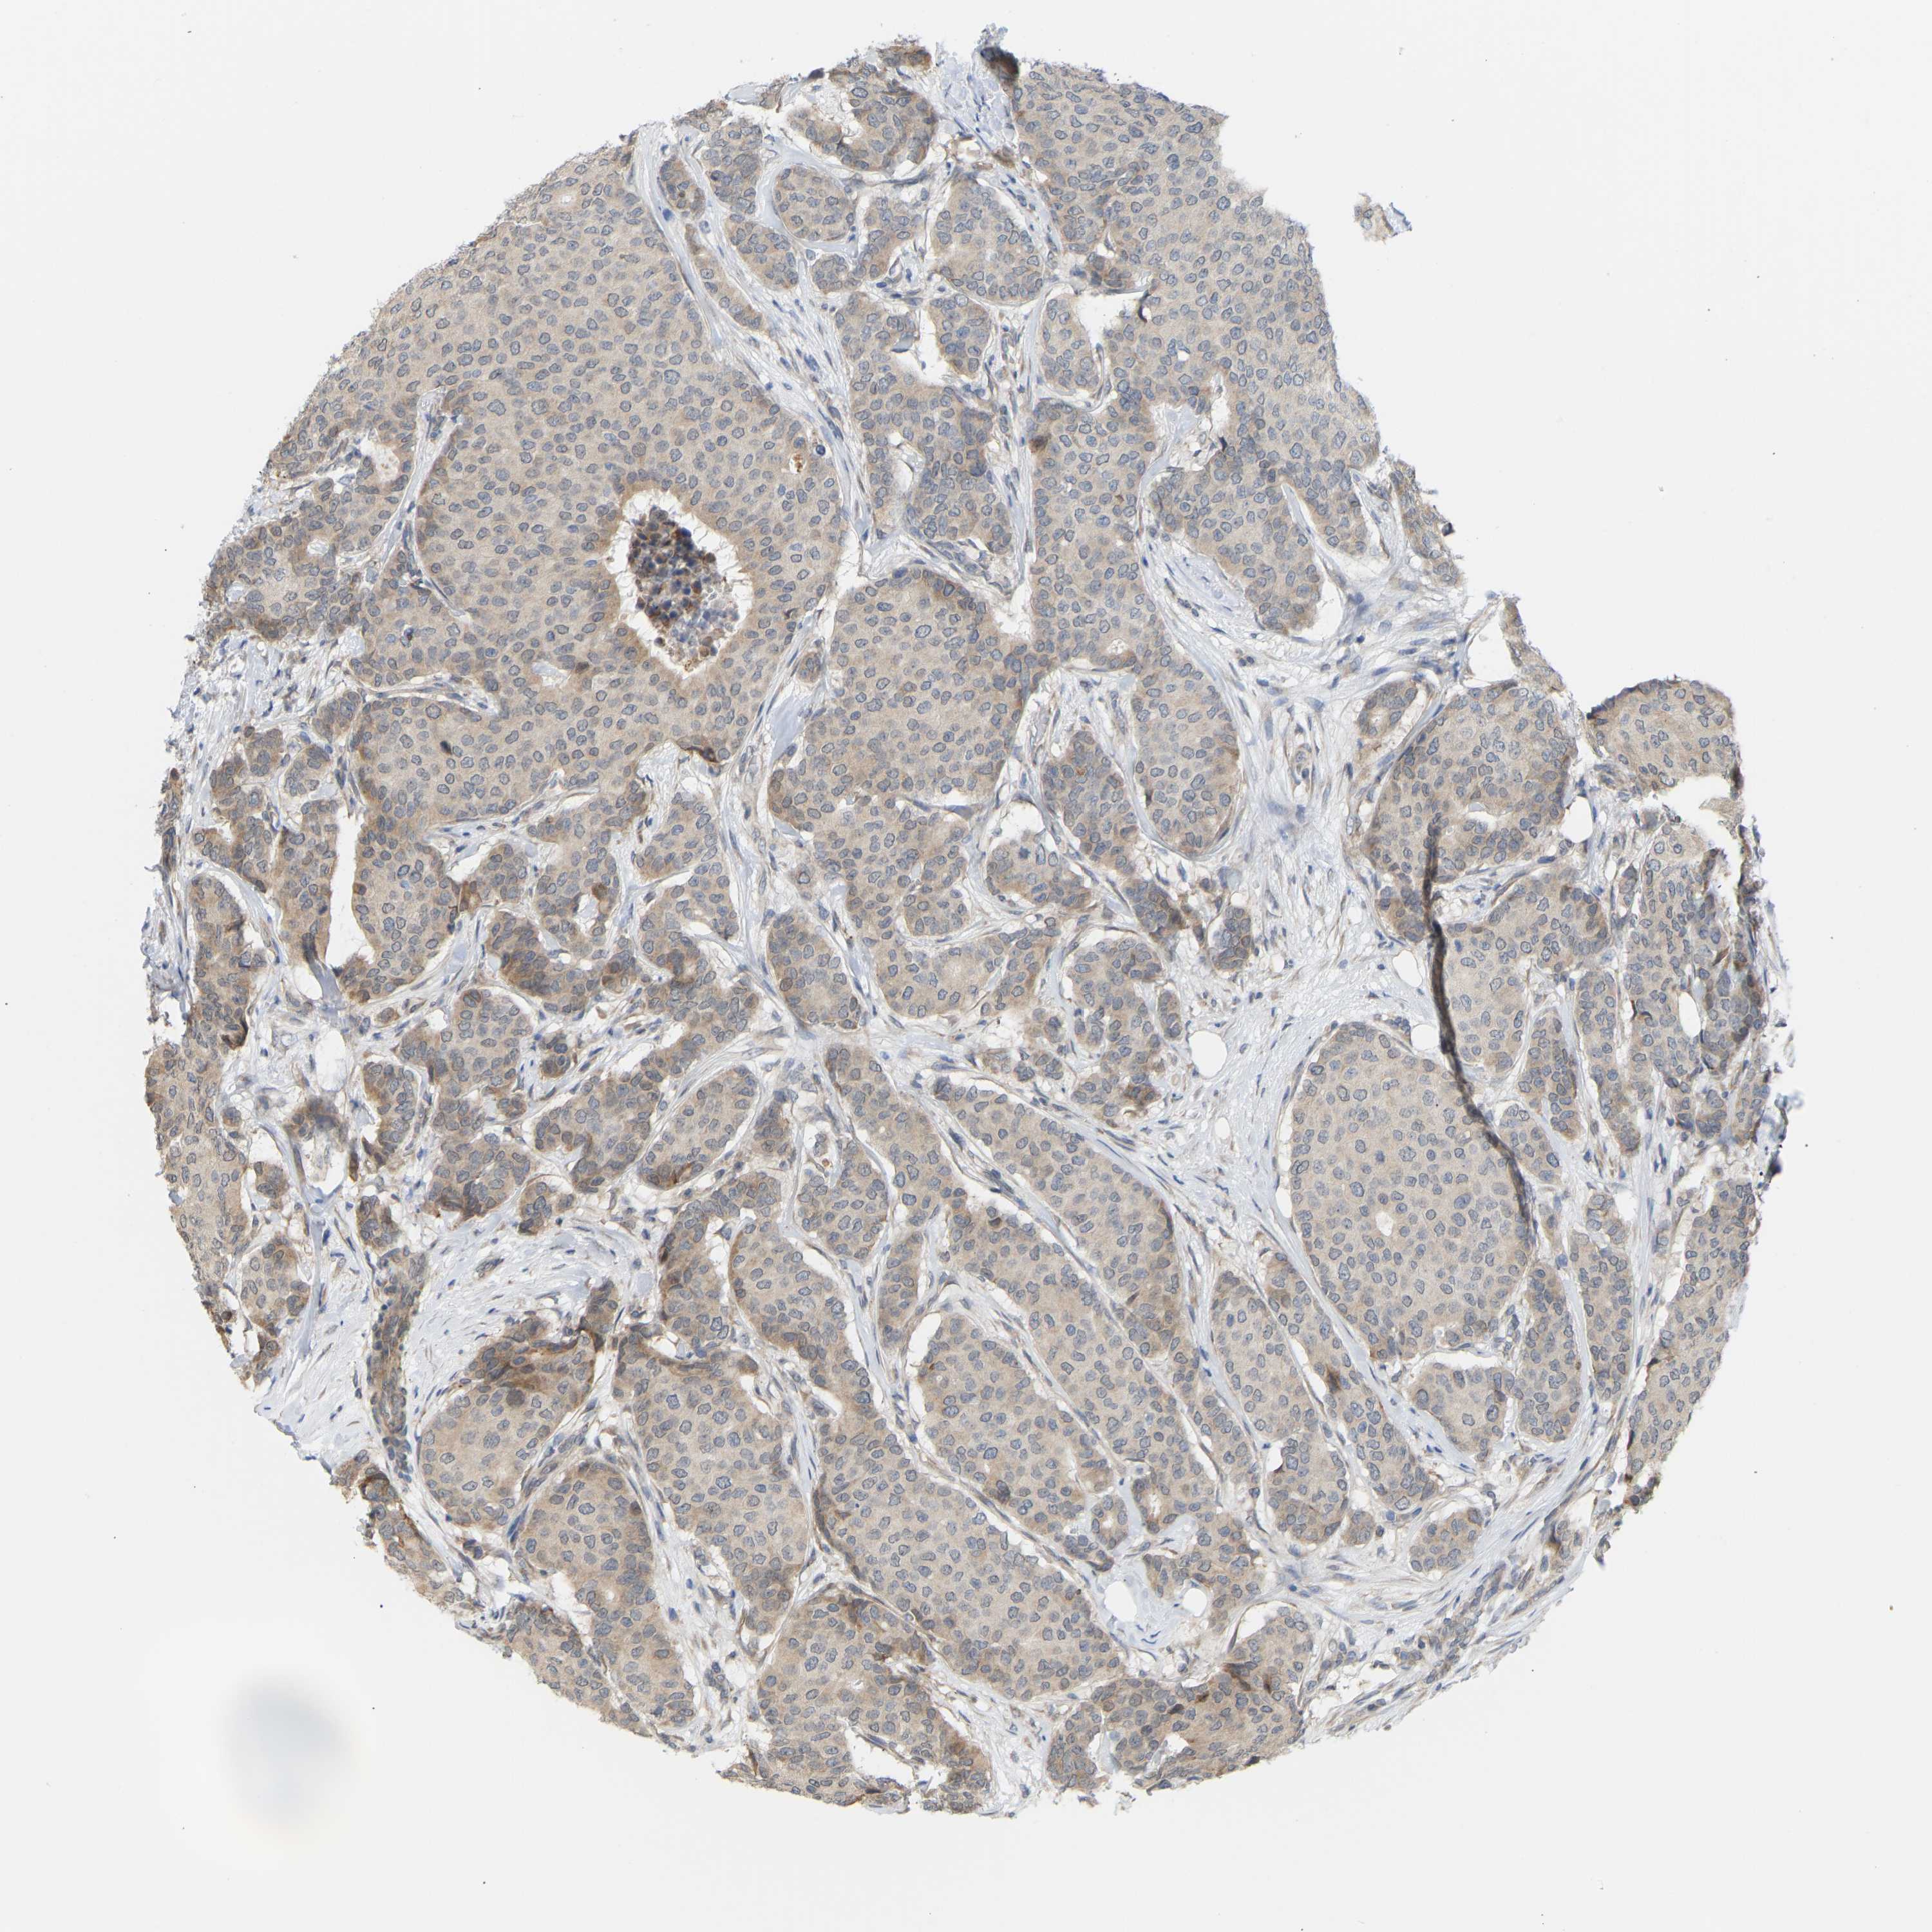

CANCER BREAST CANCER Show tissue menu

BRCA TCGA BRCA VALIDATION PROTEIN EXPRESSION